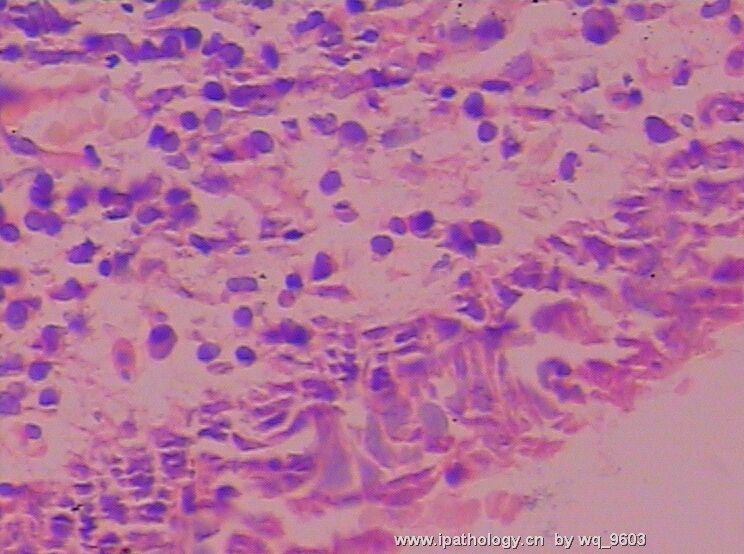

子宫颈息肉是慢性宫颈炎表现的一种,在已婚妇女中比较多见。来源于宫颈粘膜的息肉,表面有一层柱状上皮覆盖有丰富的微血管,因而颜色鲜红、柔软脆弱。轻轻触动就会出血,以至于经常发生感染而形成溃疡另有一种来自宫颈阴道部分的息肉,表面由复层鳞形上皮所覆盖,由于间质内主要为纤维结缔组织所以颜色浅红,质较韧,基底较宽病位表浅。

子宫颈是子宫下端的部分,其内腔呈圆筒形或梭形,称为宫颈管。它的上端为宫颈内口,下端为外口。宫颈管表面有一层粘膜,由于慢性炎症的长期刺激,使得颈管粘膜不断增生,堆积,并且从粘膜的基底层向宫颈的外口突出,从而形成了息肉。息肉的根部大多附着在宫颈管内或宫颈的外口,一般比较小,直径多在1厘米以下,单个或多个。也有较大者,直径可达数厘米,有蒂,随着生长而突出于宫颈口外。息肉小的,则仍留在宫颈管,仅微现于宫颈口。